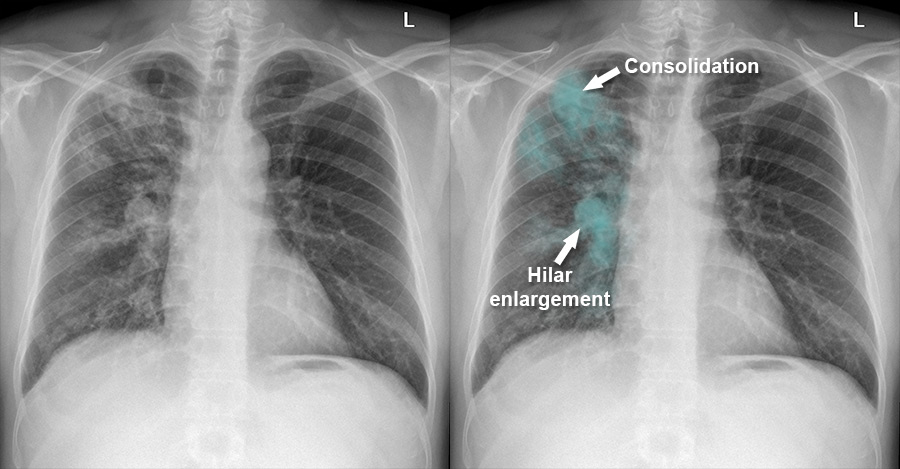

X ray of Pulmonary tuberculosis

| X ray of Pulmonary tuberculosis vs Normal chest x ray |

- Opacification

- Consolidation

- Collapse

- Cavity

- Lymph node opacity

Occasionally tuberculosis

pneumonia (caseated content drained into bronchus and then distal migration)